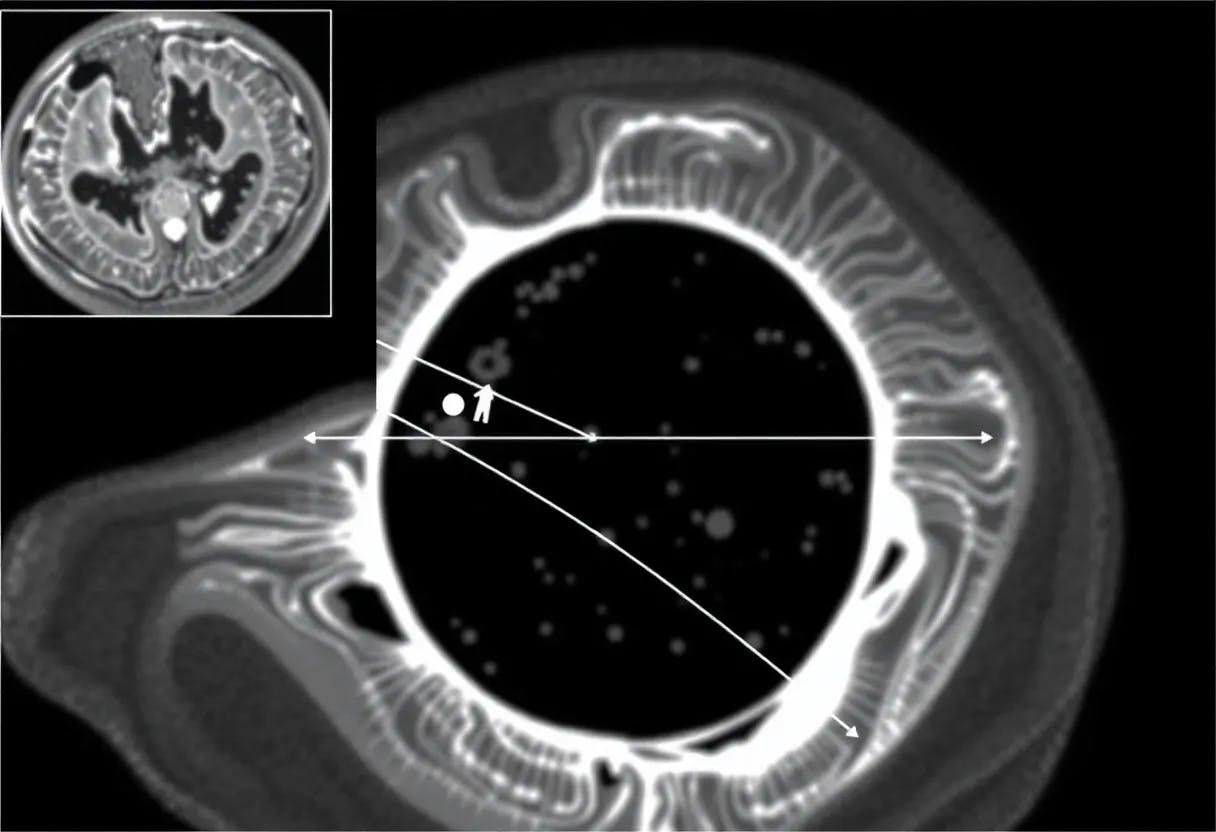

Image reconstruction for dynamic inverse problems with highly undersampled data poses a major challenge: not accounting for the dynamics of the process leads to a non-realistic motion with no time regularity. Variational approaches that penalize time derivatives or introduce PDE-based motion model regularizers have been proposed to relate subsequent frames and improve image quality using grid-based discretization. Neural fields are an alternative to parametrize the desired spatiotemporal quantity with a deep neural network, a lightweight, continuous, and biased towards smoothness representation. The inductive bias has been exploited to enforce time regularity for dynamic inverse problems resulting in neural fields optimized by minimizing a data-fidelity term only. In this paper we investigate and show the benefits of introducing explicit PDE-based motion regularizers, namely, the optical flow equation, in 2D+time computed tomography for the optimization of neural fields. We also compare neural fields against a grid-based solver and show that the former outperforms the latter.

In this paper, we investigate the performance of neural fields regularized by explicit PDE-based motion models in the context of dynamic inverse problems in CT in a highly undersampled measurement regime with two dimensions in space. Motivated by [4] and leveraging automatic differentiation to compute spatial and time derivatives, we study the optical flow equation as an explicit motion regularizer imposed as a soft constraint as in PINNs. Our findings are based on numerical experiments and are summarized as follows:

This model was further employed for 2D+time problems in [6] and [7]. In the former it is studied its application on dynamic CT with sparse limited-angles and it is studied both L 1 and L 2 norms for the data fidelity term, with better results for the former. In the latter, the same logic is used for dynamic cardiac MRI. In 3D+time domains, we mention [39] and [40] for dynamic CT and dynamic photoacoustic tomography respectively.